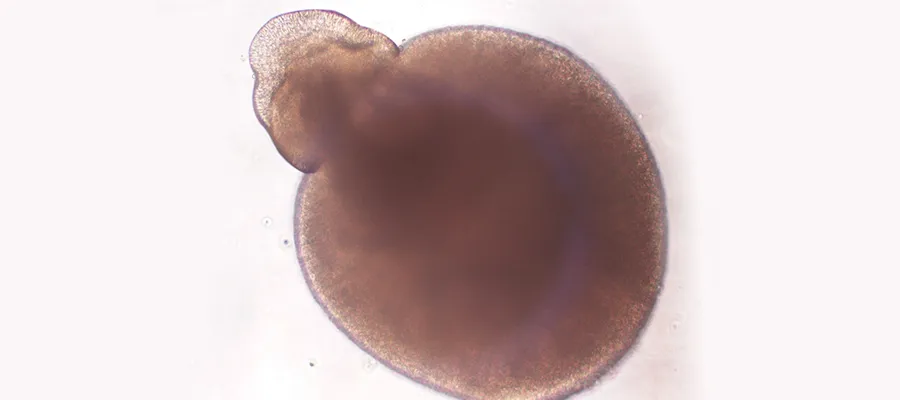

When you float stem cell colonies off their dish, allow them to form 'embryoid bodes' and pattern them towards an eye field state, an outpouching from the embryoid body occurs.